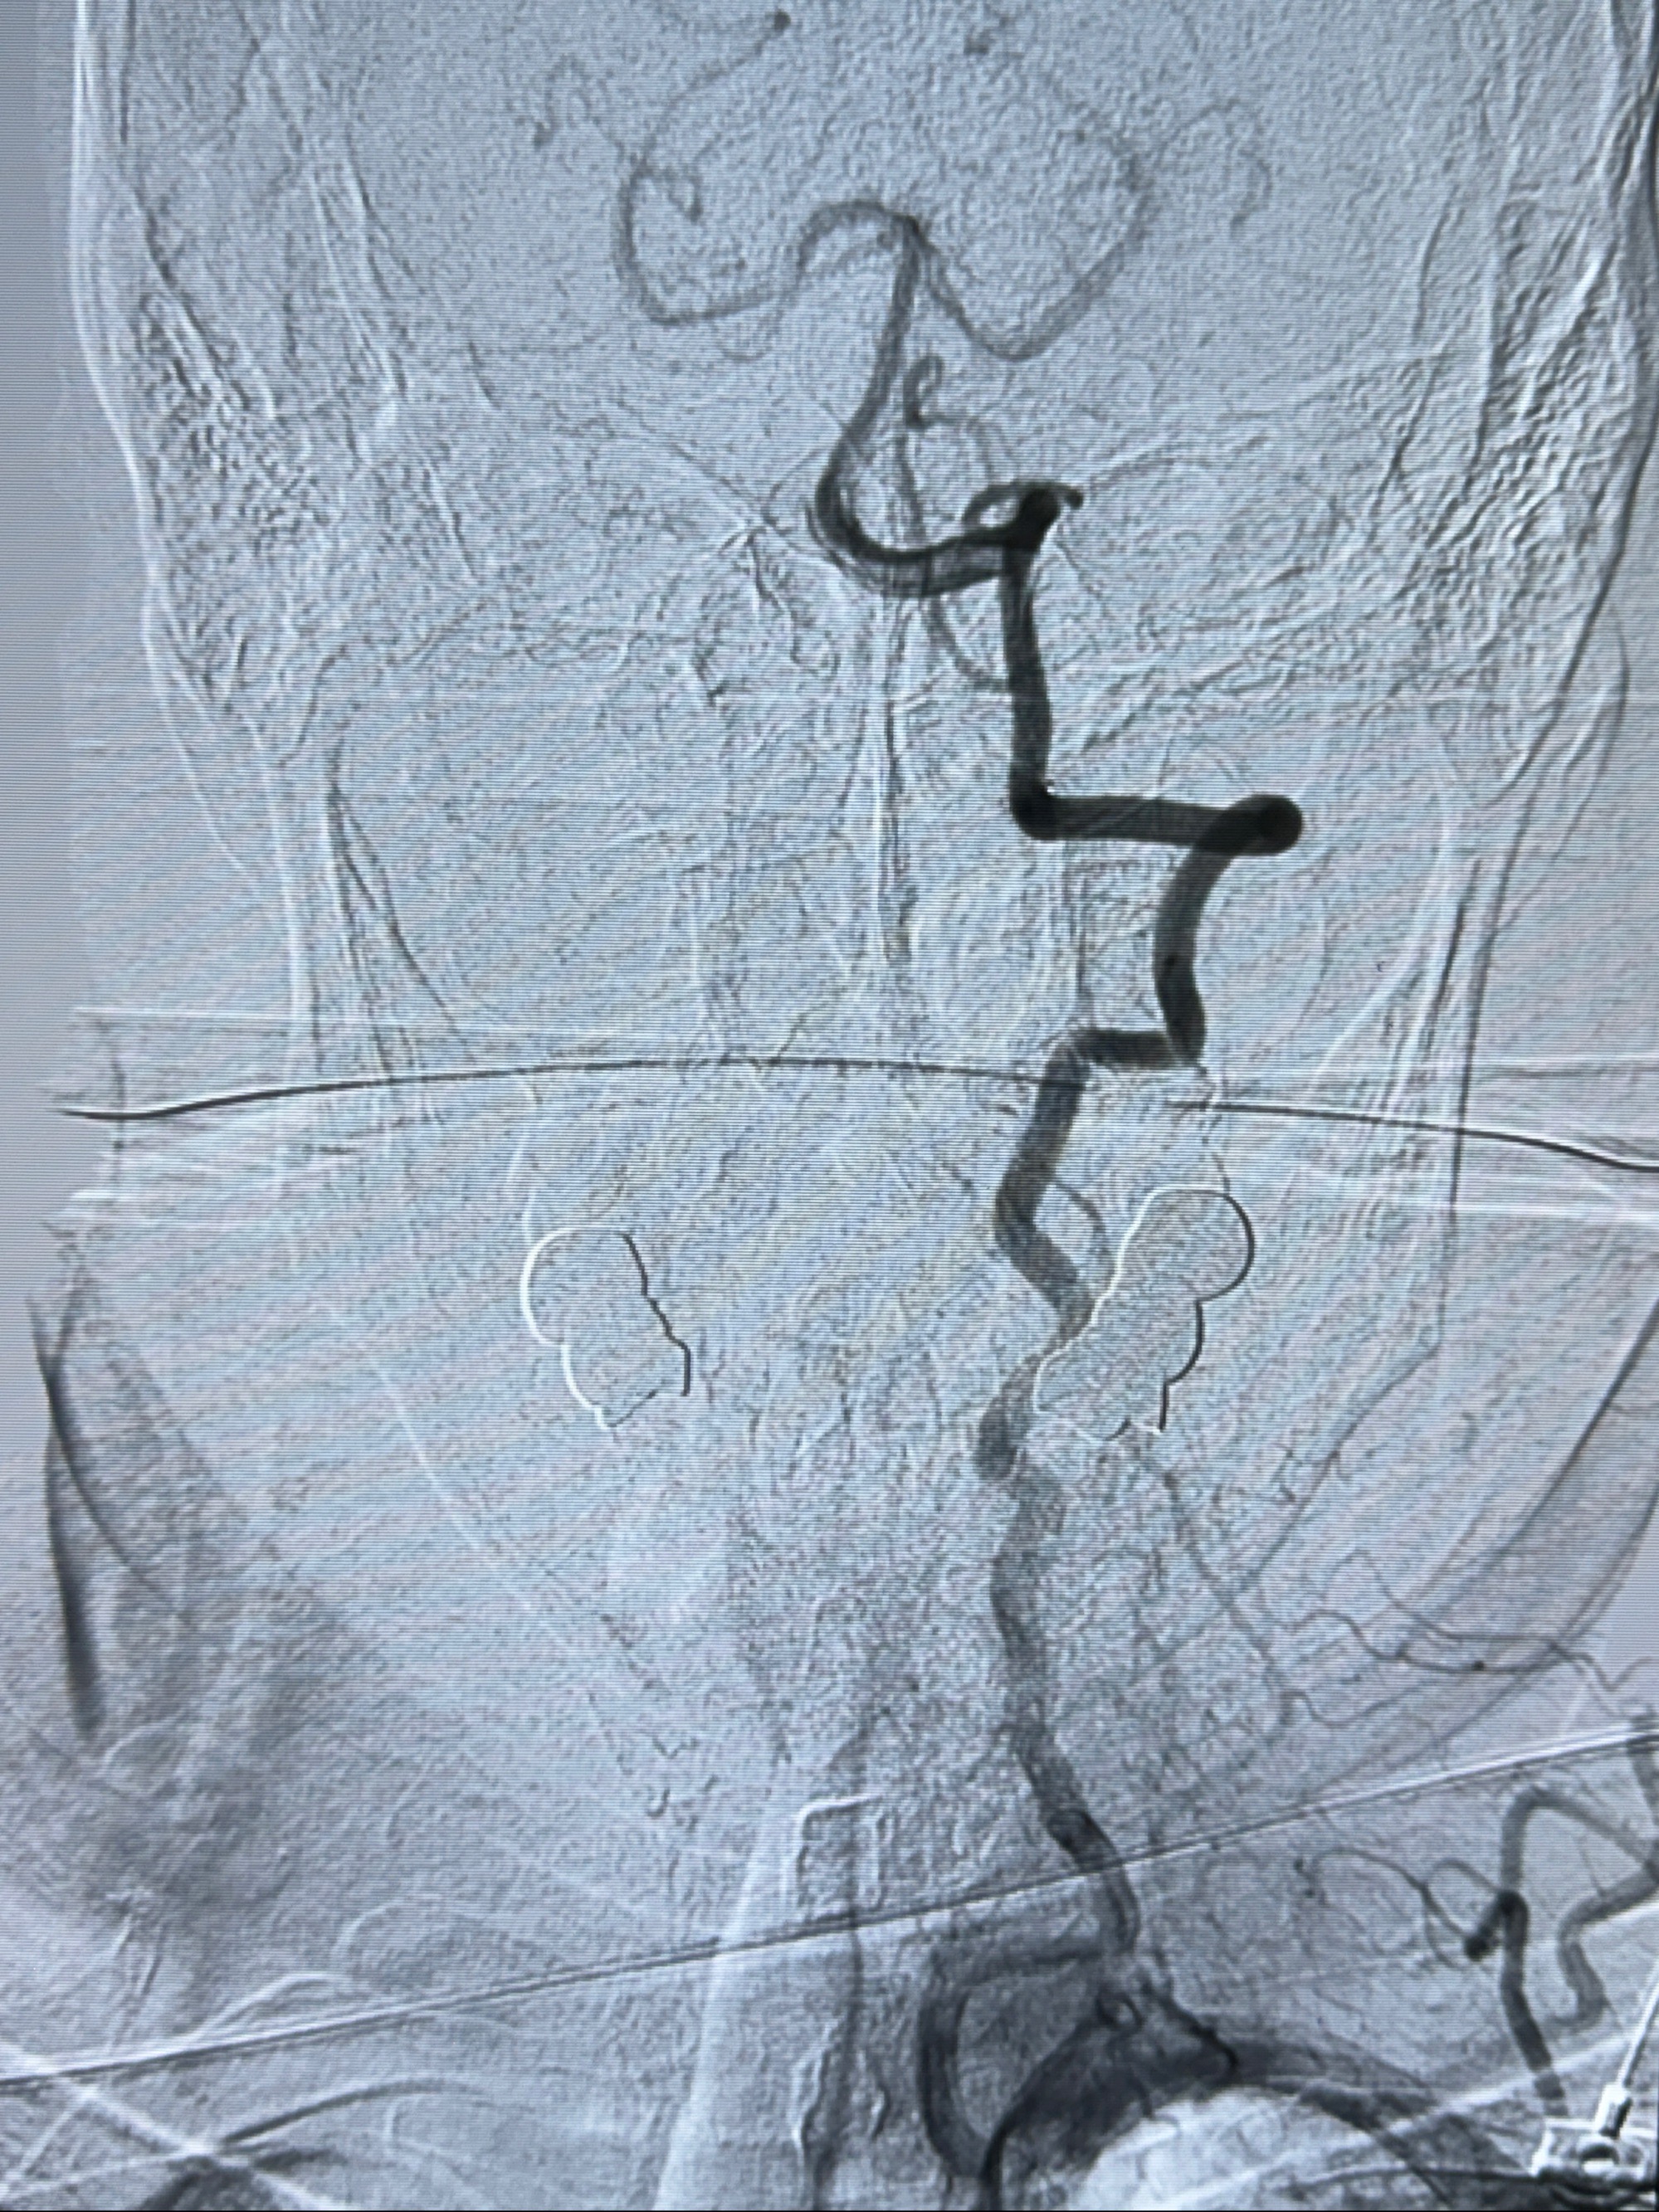

2023-11-24DSA:右侧大脑中动脉下干起始部动脉瘤,约2.3*2.5mm,形态规则

2023-12-04全麻下行支架辅助治疗

S-AB4-20mm